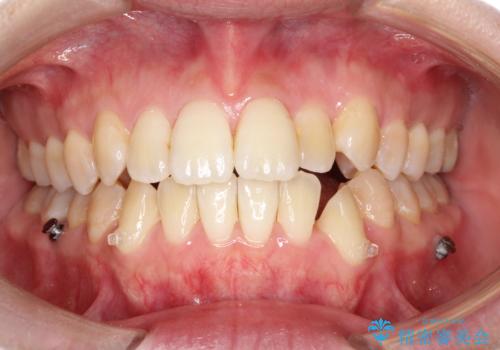

- 前歯のガタガタと、かみ合わせを改善したいとのことで来院されました。

人前でお話をするお仕事のため、装置をつけないでよいマウスピース矯正を希望されました。

下顎の歯が、上顎の歯に対して前方に位置していたので、下顎の歯を後方に移動させるのと、歯と歯の間を削りスペースを作り、歯を並べる計画としました。

お仕事の関係で使用時間が制限されるときもあり、治療期間が予想より少し長くなりましたが、装置をつけずに治療を終えることができました。